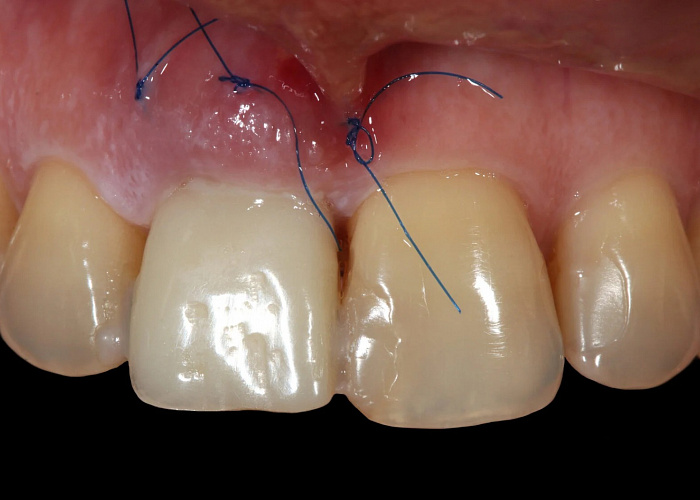

Хирургическое устранение рецессий десны. Восстановление межзубного сосочка. Показания. Методики. Разбор ошибок и осложнений.